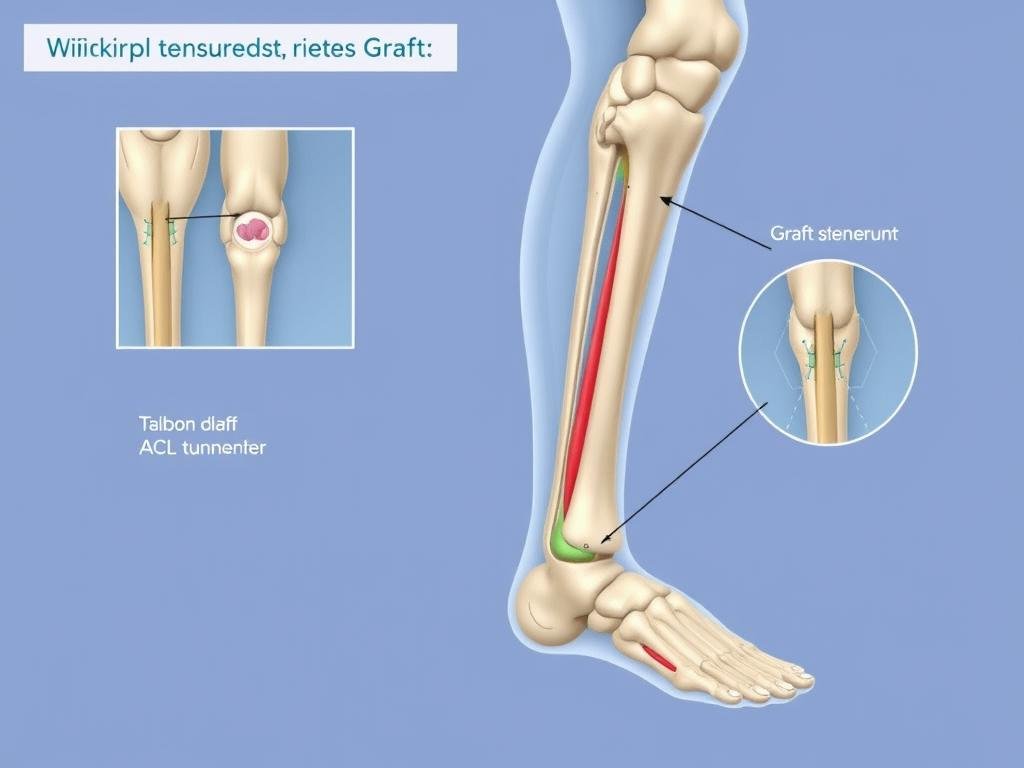

Bei diesem Verfahren wird das gerissene Kreuzband durch ein körpereigenes Sehnentransplantat ersetzt. Als Transplantate kommen in Frage:

Das Transplantat wird durch Bohrkanäle im Ober- und Unterschenkelknochen gezogen und fixiert. Es wächst im Laufe der Zeit ein und übernimmt die Funktion des Kreuzbandes.

Kreuzbandplastik: Einziehen des Sehnentransplantats durch Bohrkanäle im Ober- und Unterschenkelknochen